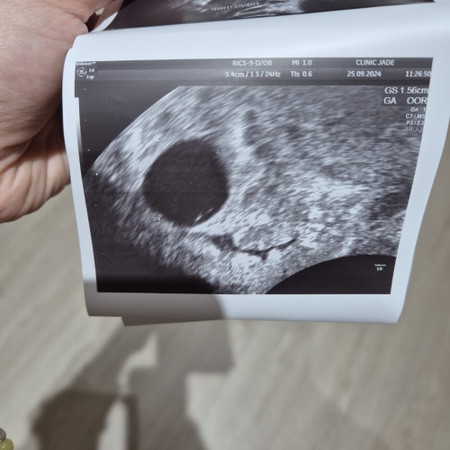

7 weeks scan & empty sac

Hi mummies! I had a scan about a week ago but doctor said he could not see yolk sac or fetal pole. I thought I was 7-8 weeks but doctor said could be early and I'm going for another scan next week. Photo attached my scan. Any thoughts or success stories would be greatly appreciated.

We had the same issue. My wife’s scan looked exactly like yours. Then it ended up being too early. Just wait a couple weeks and it’ll show!